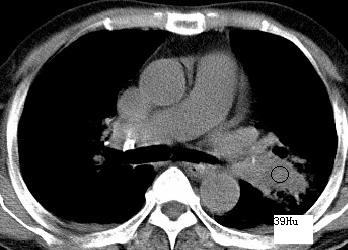

以下是引用xianxianzhongyi在2008-4-20 14:44:00的发言:[br]本人愚见:次病例短短两月的时间,呈现如此大面积实变,病变增长过于迅速,此其一。其二,病变在动脉早期既有明显强化。其三,左上叶后段及下叶背段多叶受累。其四,肺门及纵隔内未见明显肿大的淋巴结。估计层面较厚段支气管显示不清。 诊断:炎性实变可能性大。

以下是引用光影相伴在2008-4-20 14:39:00的发言:[br]支持:1)左侧中央型肺癌伴左肺上叶阻塞性肺炎。、[br] 2)双侧少量胸腔积液。